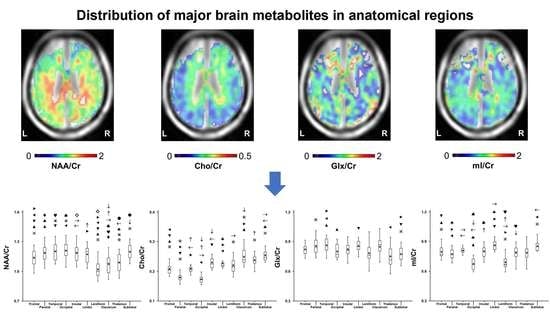

2.1. Variation in Metabolite Ratios with Anatomical Location